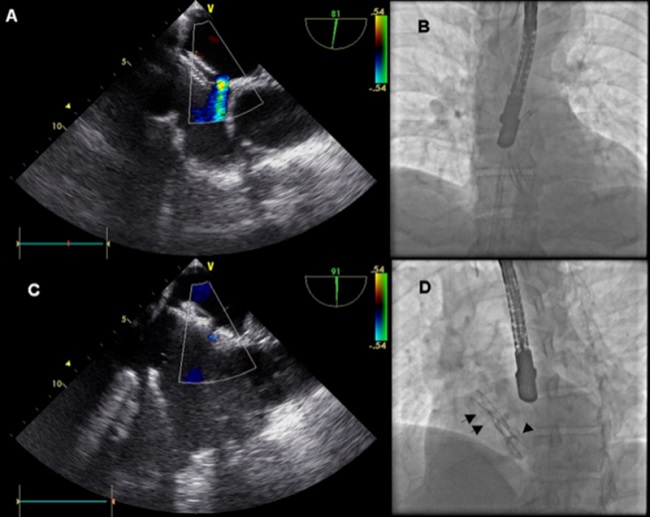

Durante la intervención percutánea bajo guía con ETE, se observó un gran aneurisma hipomóvil del septum interauricular con un FOP distendido de tamaño grande (3 mm) y un defecto adicional pequeño y cercano al FOP de 5 mm de diámetro. Se implantó un dispositivo Nit Occlud PFO (pfm Medical, Colonia, Alemania) de 30 mm de disco y previo a la liberación se observó que cubría el defecto adicional. Sin embargo, después de liberar el dispositivo, la comunicación interauricular (CIA) persistía, de localización anterosuperior y de tamaño moderado (12 mm de diámetro) (Figura 1a).

Debido a que no se podía tolerar la persistencia de cortocircuitos residuales, se avanzó un catéter a través del defecto residual (Figura 1b) y se implantó un dispositivo Nit Occlud ASD-R (pfm Medical, Colonia, Alemania) de 18 mm de diámetro. El segundo dispositivo fue posicionado abrazando el primer dispositivo logrando la oclusión completa de ambos defectos (Figura 1c). El paciente fue dado de alta al siguiente día sin complicaciones. A los 9 meses de seguimiento, no hubo recurrencia de eventos ni arritmias y ambos dispositivos se encuentran normo posicionados. (Figura 1d).